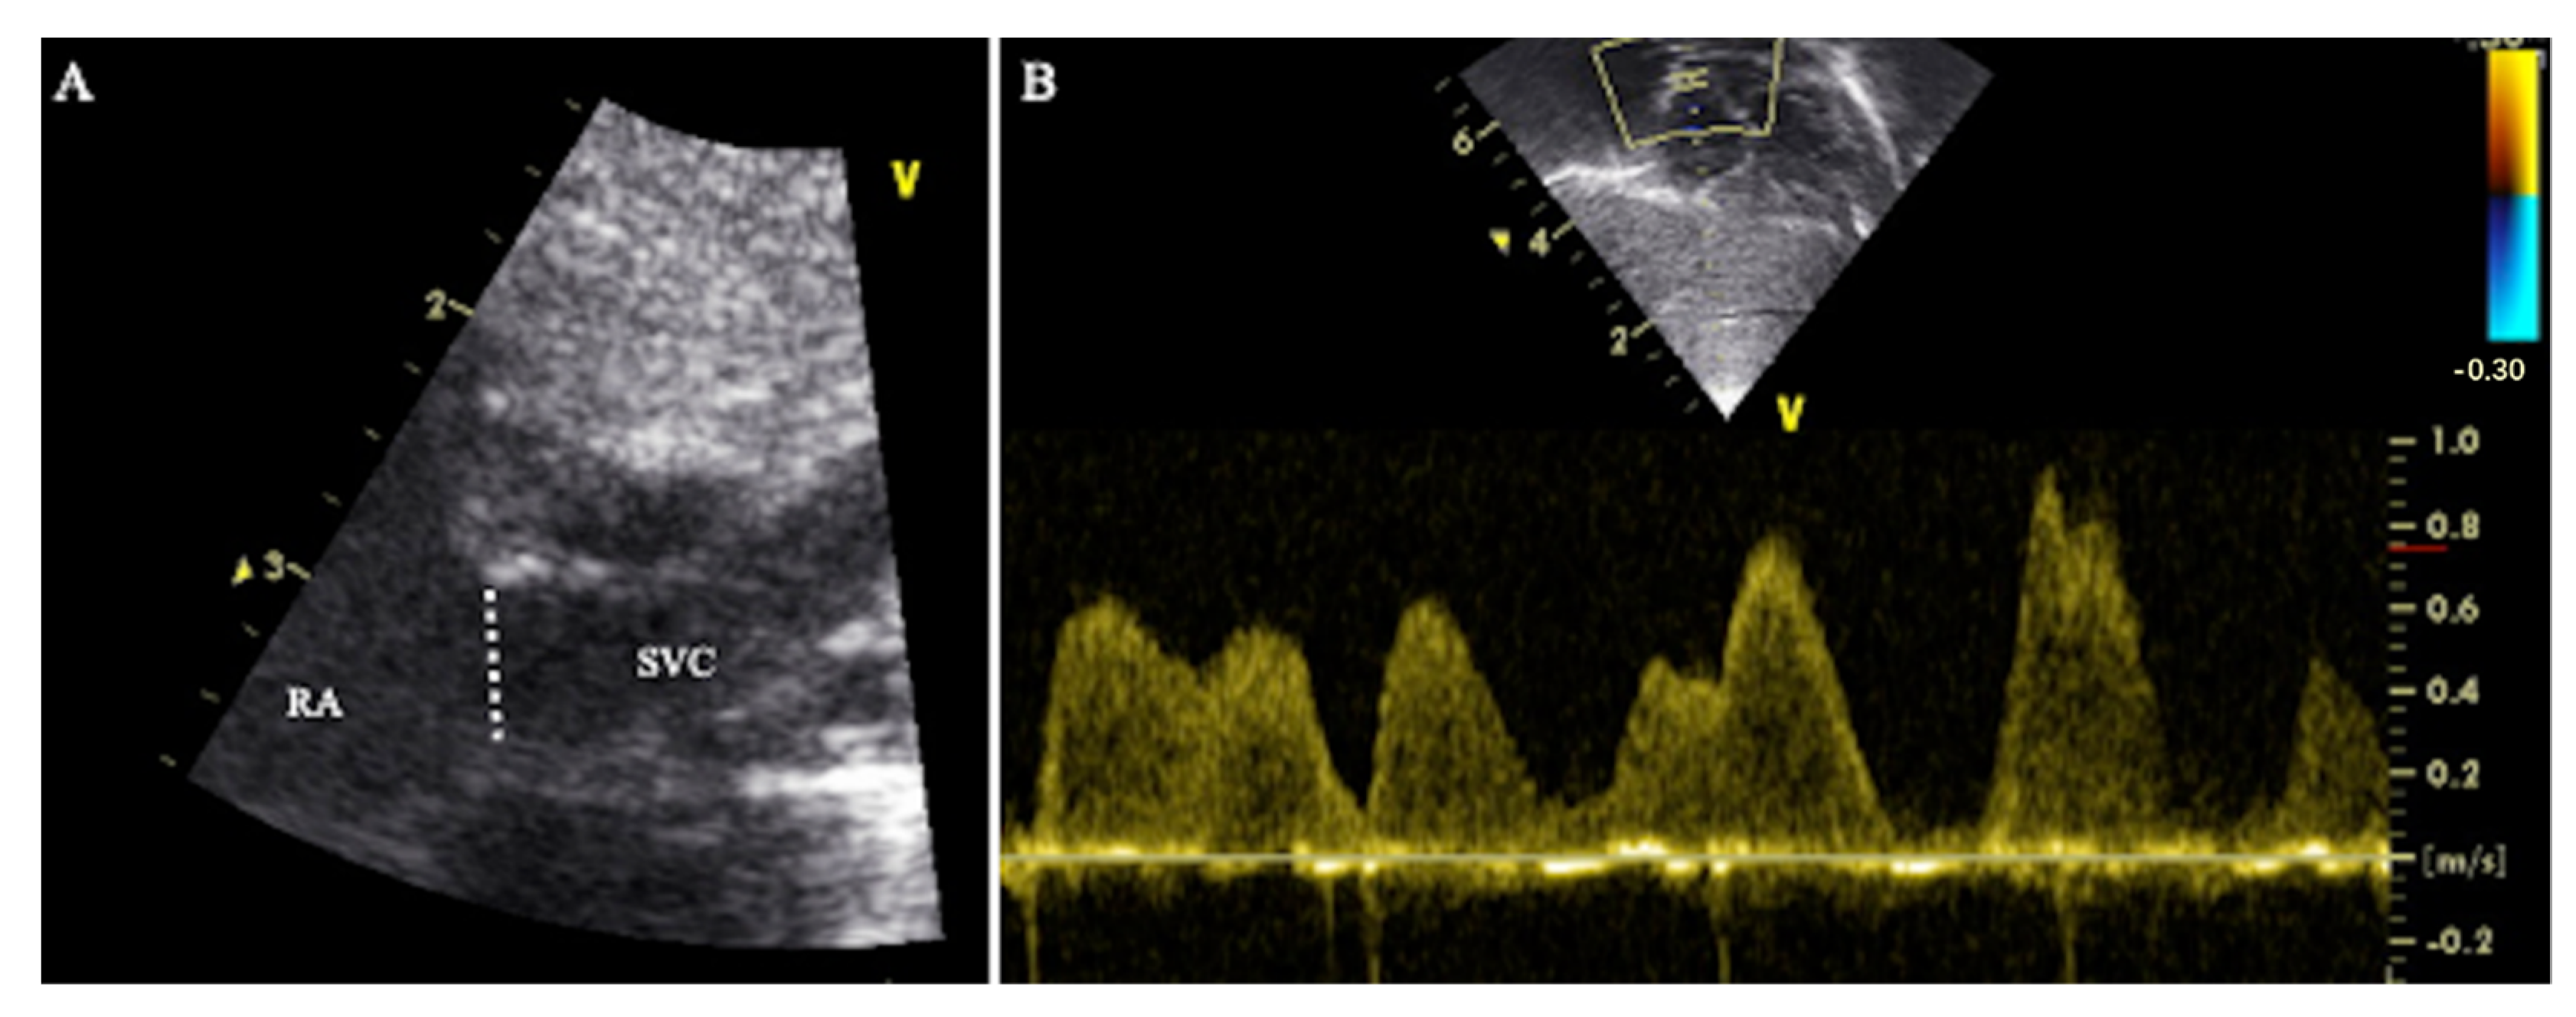

2.2.1. Method 1—Traditional Superior Vena Cava Flow Technique

2.2.2. Method 2—Modified Superior Vena Cava Flow Technique

2.2.3. Method 3—Modified Superior Vena Cava Flow Technique